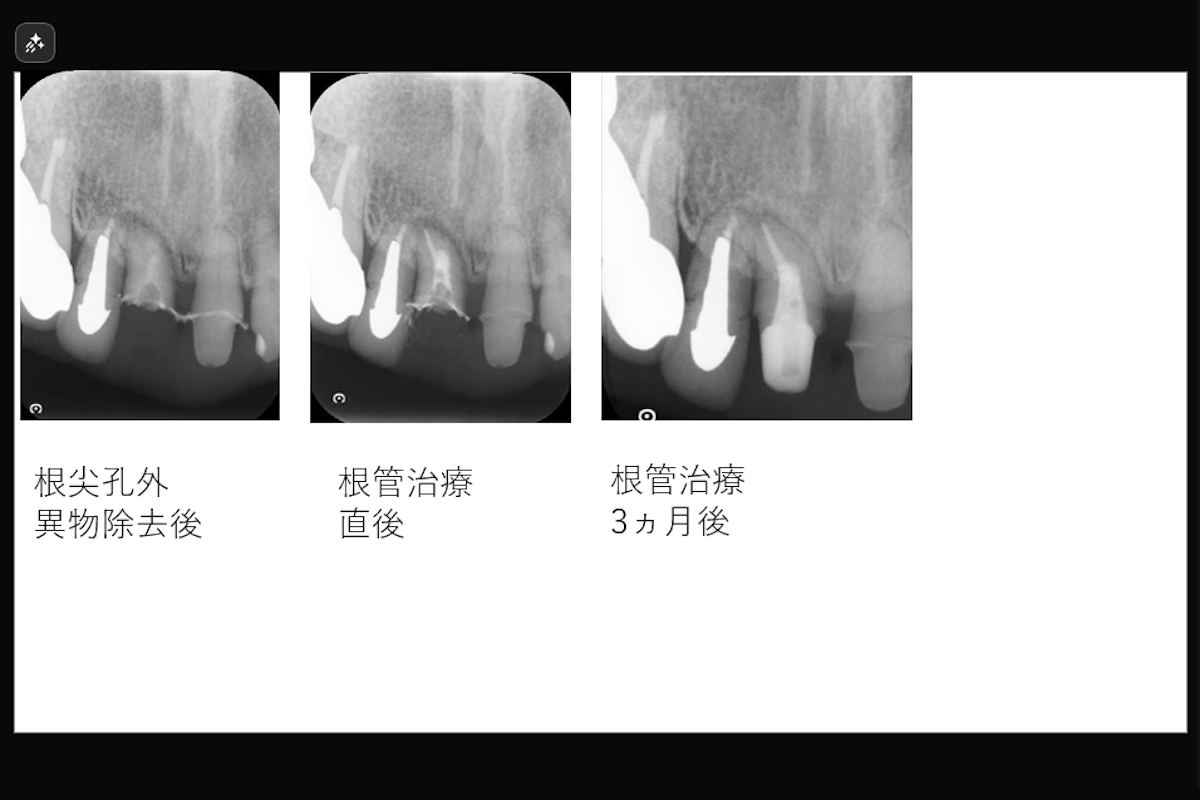

治療期間: 約2か月

治療費目安: およそ19万円 (再根管治療、根尖孔外異物除去、穿孔修復)

治療内容:上顎右側中切歯 根管治療(穿孔修復、根尖孔外異物除去)

治療のリスク: 残存歯質の厚みによって歯根破折のリスク、経過によっては外科的歯内療法